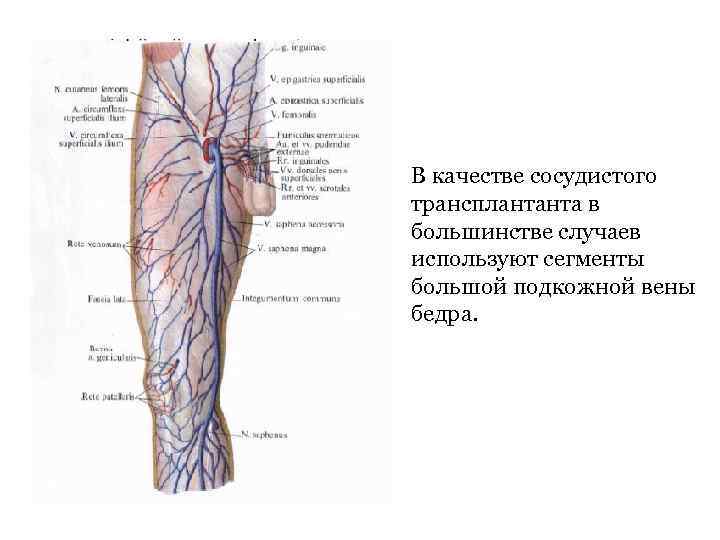

• В качестве сосудистого трансплантанта в большинстве случаев используют сегменты большой подкожной вены бедра.

• В качестве сосудистого трансплантанта в большинстве случаев используют сегменты большой подкожной вены бедра.

• После АКШ с использованием собственной вены в сроки от 3 до 5 лет в 28 -35 % случаев наблюдают тромбоз или окклюзию шунтов, что приводит к стойкому рецидиву стенокардии.

• После АКШ с использованием собственной вены в сроки от 3 до 5 лет в 28 -35 % случаев наблюдают тромбоз или окклюзию шунтов, что приводит к стойкому рецидиву стенокардии.

• Выполнение такой операции затруднено у больных с заболеванием вен нижних конечностей (варикозная болезнь, тромбофлебит)

• Выполнение такой операции затруднено у больных с заболеванием вен нижних конечностей (варикозная болезнь, тромбофлебит)